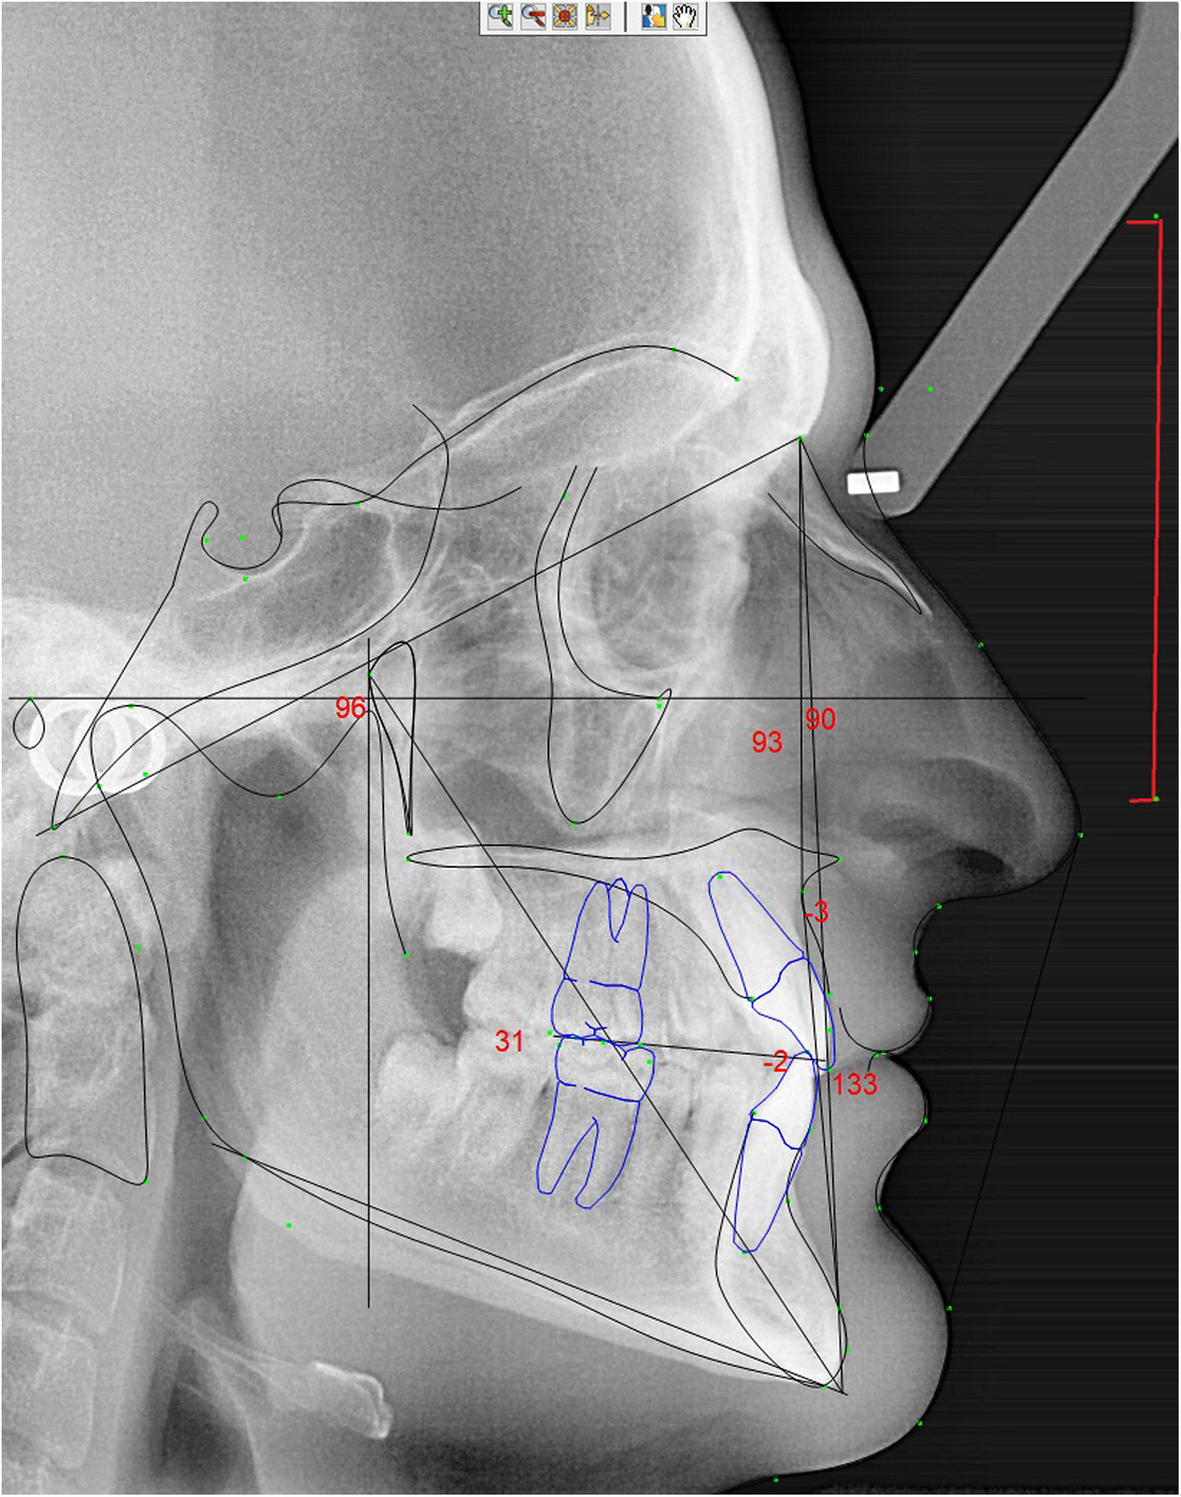

Rickett’s cephalometric dots and plans of an instrumentalist